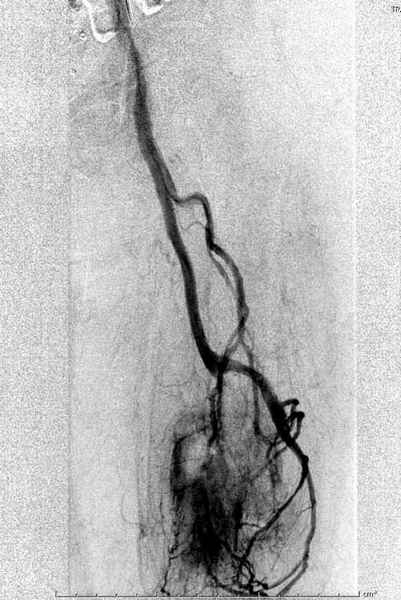

В зависимости от характера опухоли некоторые патологические переломы имеют риск кровотечения во время операции. Множественные литературные данные подтверждают, что надо проявить осторожность при интрамедуллярном остеосинтезе при неизвестных опухолях, особенно где имеется подозрение на Renal Cell Carcinoma. (RCC- hypernephroma) http://www.bonetumor.org/tumors/pages/page64.html

Со слов, больная ничем не болела, только последние 3 месяцев чувствовала боли в бедренной области. КТ брюшной полости подтвердил увеличенную правую почку. (5-6)

Для предупреждения кровотечения во время рассверливания, за день до операции провели эмболизацию сосудов питающий метастаз. http://radiology.rsnajnls.org/cgi/reprint/150/3/673.pdf (7-11, 12-15-16)

Кровопотеря во время операции меньше 100 мл.